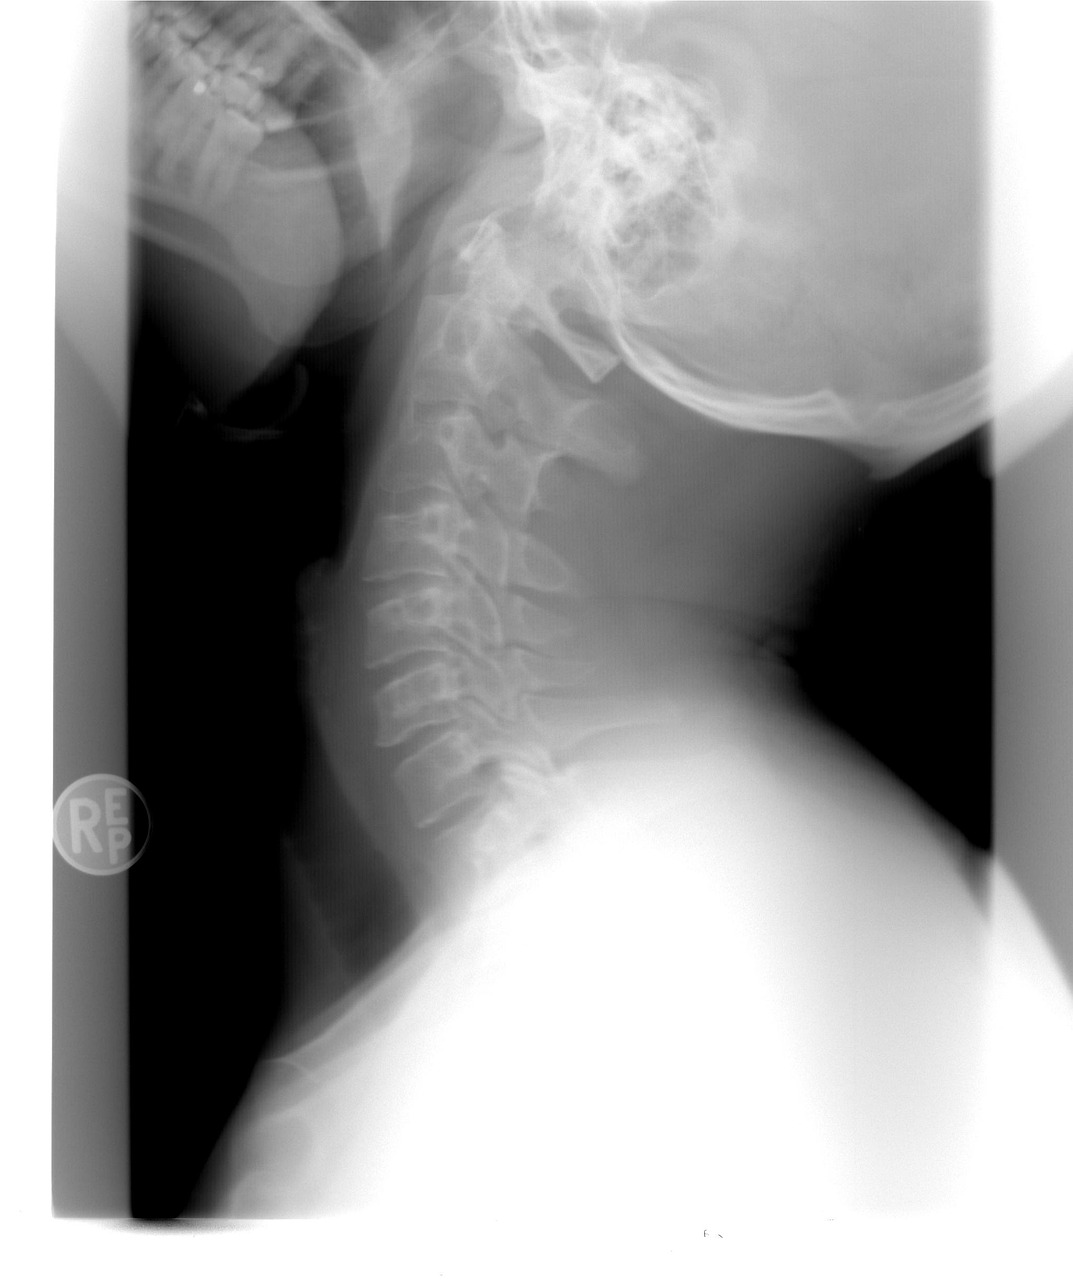

| CT/MRI | 뇌혈관, 폐 질환 등 고위험군 정밀 진단 |